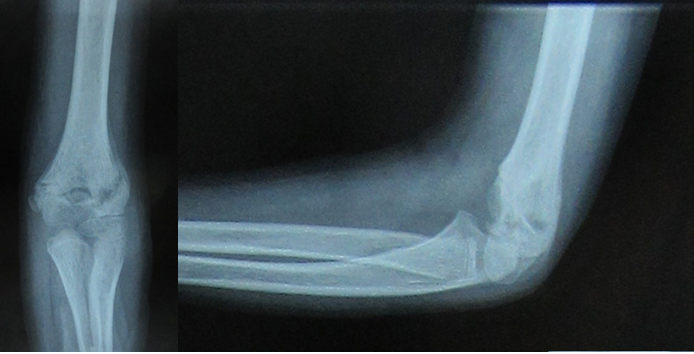

All the fractures united with no loss of carrying angle or cubitus varus deformity. According to Flynn’s grading system for elbow function, 41 patients (89.1%) achieved excellent results and one patient had poor result as shown in Table 2. Five patients (10.8%) had superficial pin site infection that went to heal with local pin site dressings only. None of them had chronic discharge after the wire removal. No complications like ulnar nerve injury, vascular injury, compartment syndrome, myositis ossificans, malunion, and non-unions were noted (Figures 1-4).

Figure 1 Pre-operative X-rays of the elbow.